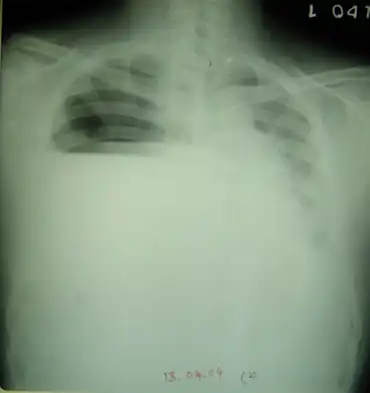

| Arcanobacterium haemolyticum colonies on a blood agar plate: Beta-hemolysis is demonstrated with transmitted light. | |

Hemolysis is detected on human blood agar plates, and routine plating of specimens suspected of containing A. haemolyticum on human blood agar is suggested to distinguish it from Streptococcus pyogenes, as A. haemolyticum can easily be confused with this organism. Microscopic morphology differences can be used to differentiate them, since Arcanobacterium is rod-shaped and Streptococcus is coccus-shaped.[4]